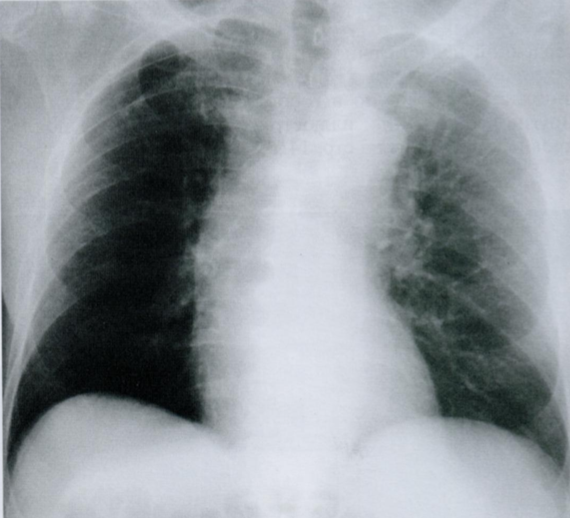

На снимке в правом легочном поле мы видем участок инфильтрации. Справа легкое имеет три доли. В данную проекцию попадают СД и НД. В какой из них расположена инфильтрация и почему Вы пришли к такому выводу?

Запомните: если на фоне измененного легочного рисунка виден силуэт сердечной тени - затенение распологается в заднем отделе НД, а если силуэт не определяется - в переднем отделе СД.

КТ на уровне правого предсердия (2), с инфильтрацией (37) в СД (33), которая соприкасается с ПП (2).

Инфильтрация и окружающих отек повышают плотность легочной ткани до плотности, эквивалентной сердечной тени.

В результате граница между инфильтратом и контуром сердца не визуализируется.

Ответ: инфильтрат раполается в переднем отделе СД правого легкого.